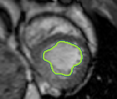

4.2 Visual assessment

We select the case that achieves the highest and lowest dice score for visual assessment. Fig. 4 shows example segmentation results where the proposed method achieved the highest agreement with the ground truth delineations. Fig. 5 shows example segmentation results where the proposed method achieved the lowest agreement with the ground truth delineations.